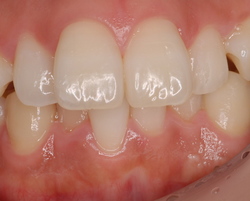

上の左右2番目の歯が内側にたおれているのをきれいにしたいという患者さんでした。

最初の状態

矯正をするか、かぶせで治すか、ということでいろいろ話合い、ラミネートべニアで治療しようということに決まりました。